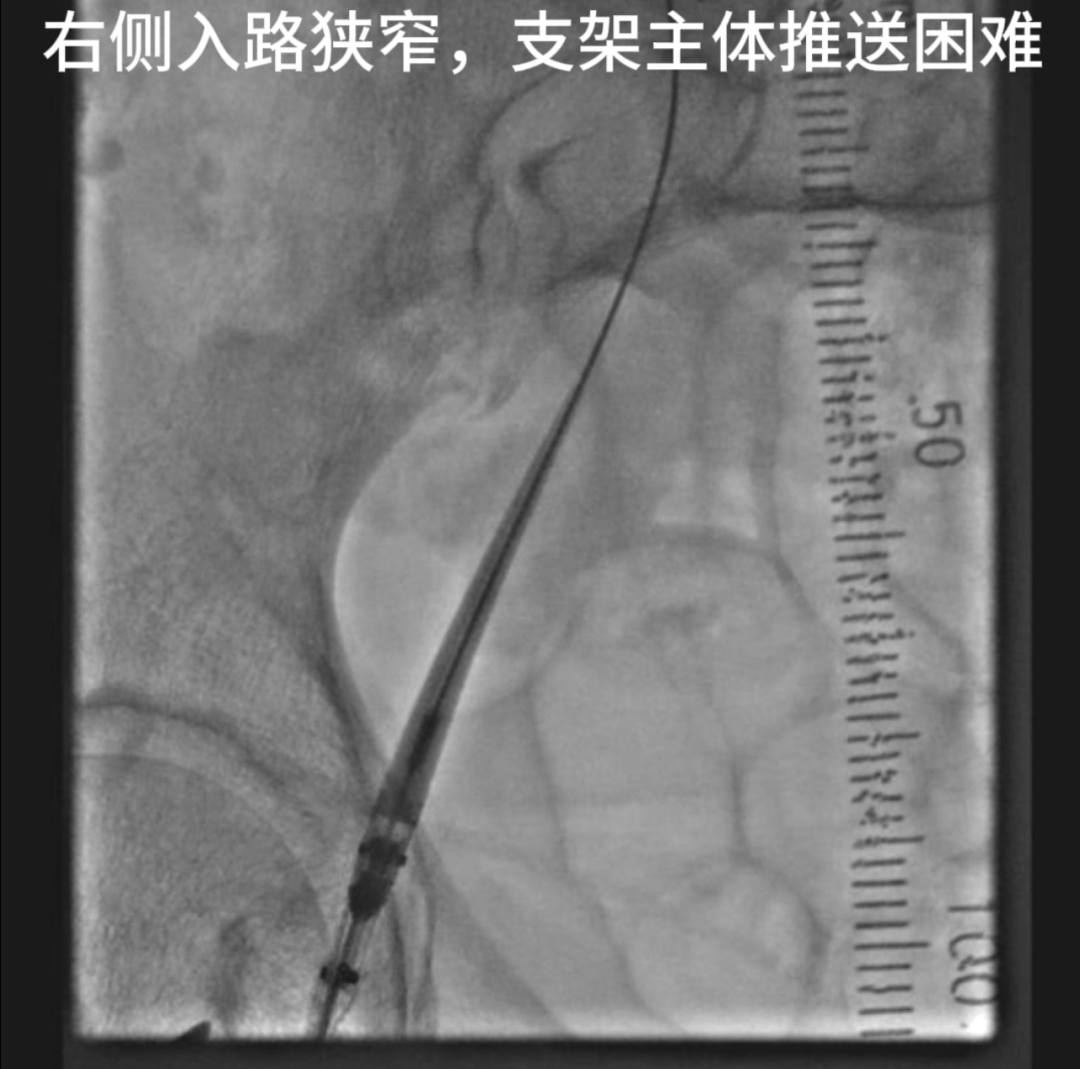

支架植入与入路管理

经右侧股总动脉植入主体支架及髂支,保留右侧髂内动脉血供。右侧髂外动脉直径仅5mm,需通过18F(约6mm)输送系统,因血管无严重钙化且走行较直,尝试球囊扩张后成功推送支架,避免了腹膜外切口及人工血管构建。

1. 入路狭窄处理

右侧髂外动脉5mm管腔通过6mm输送系统时,采用预扩张策略:使用6mm球囊对髂外动脉进行短暂扩张,利用血管弹性代偿,成功完成支架输送,避免了血管损伤或中转开放手术。